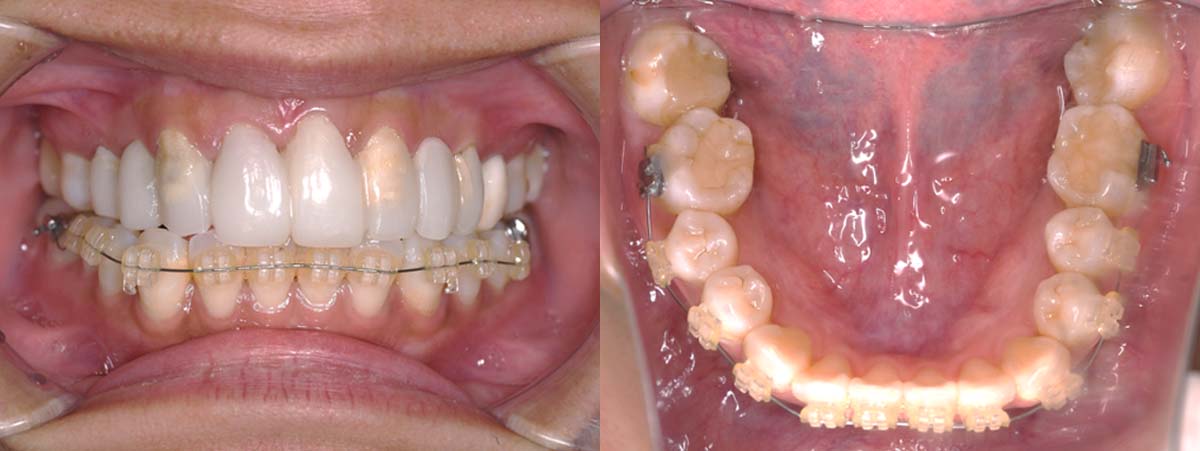

2月20日

3月13日

4月24日

9月25日